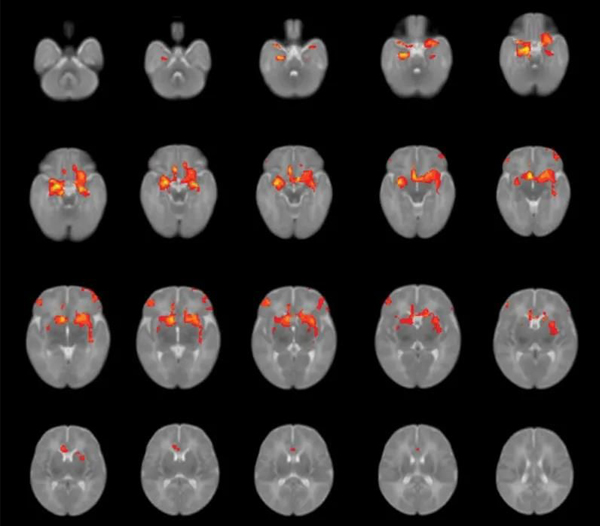

Over the past two years, several small-scale studies has been revealing that the generation born during the epidemic has been affected in many ways, even if they are not infected with the virus.

Researchers compared babies born during the pandemic with pre-pandemic data, they found that these "COVID generation" babies generally scored lower on average on tests of gross motor, fine motor and communication skills. This trend has nothing to do with whether the baby's parents are infected with the COVID, which means that the epidemic environment may be the key problem.

At the same time, the enormous stress the mother experiences during pregnancy may be a major factor that negatively affects the brain development of the fetus.

Researchers at the University of Calgary in Canada surveyed more than 8,000 pregnant women during the outbreak. Nearly half reported symptoms of anxiety, and one-third had symptoms of depression — a much higher rate than in the years prior to the outbreak of Covid-19.